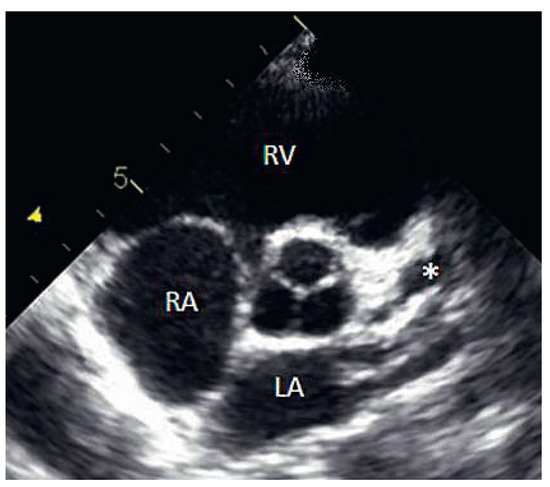

On the tenth day, we performed transthoracic echocardiography (Figure 1 and Figure 2), which revealed normal biventricular size and function, without hypokinesia. There was no pericardial effusion, no valvular disease, but a proximal enlargement of the left anterior descending coronary artery (LAD) was visualised. On the same day, because all these elements suggested Kawasaki disease (KD), treatment with intravenous polyvalent immunoglobulin (IVIG 2 g/kg as a single infusion: Privigen 70 g) and high-dose aspirin (80 to 100 mg/kg/d: 750 mg four times a day for eight days) was started, with rapid resolution of symptoms and apyrexia within 24 hours. Cardiac computed tomography (CT; Figure 3) showed three-vessel aneurysmal coronary artery disease (CAD) including a giant aneurysm of the proximal LAD (9 mm), an aneurysm of the circumflex artery (6 mm) and two aneurysms of the right coronary artery (4 and 5 mm). There was no vascular involvement in the cerebral and abdominal magnetic resonance imaging (MRI).

Figure 1.

2D echocardiography (* = left anterior descending artery aneurysm).